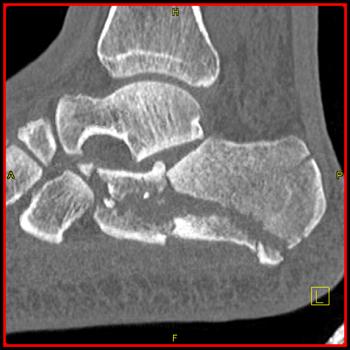

Foot Pathology: Calcaneal fractures

The calcaneus is the most commonly fractured tarsal bone. Calcaneal fractures are classified as intraarticular and extraarticular. The intraarticular fracturesaccount for 70-75% of calcaneal fractures and carry a worse prognosis. The inciting trauma is usually a fall or motor vehicle accident, and these fractures are bilateral in 10% of cases. Concomitant ipsilateral lower extremity fractures are present in 20-46% of cases, and spinal fractures in 10-30%. Extrarticular fractures (Figure: extraarticular fracture of calcaneus) account for 25-30% of calcaneal fractures, and are the sequela of a twisting injury. Anatomic regions affected include the anterior or medial process, the sustentaculum tali, the body or the tuberosity. Severe fractures are readily evident on conventional radiographs; however, CT is essential for elucidating the extent of injury. The intraarticulur fractures are often comminuted and may be displaced. CT is also used for follow up after fracture treatment. CT is very helpful for detecting fracture malunion or nonunion . In addition, the presence and extent of secondary osteoarthritis is readily detected by CT. Several features of intraarticular fractures which can be elucidated on CT have been shown to correlate with the outcome. A central depression fracture has a worse prognosis than a tongue-type fractures, but a better prognosis than a comminuted fracture. An unsatisfactory result is more likely in the setting of subtalar incongruity, decreased fibulocalcaneal space and osteoarthrosis of the talonavicular joint and the ankle.